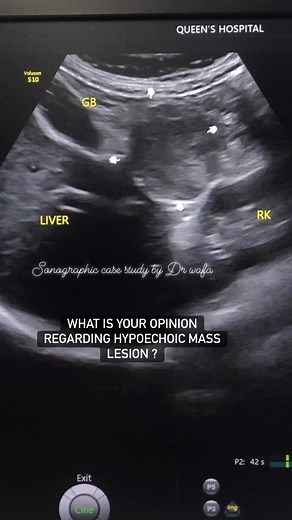

30K views · 176 reactions | #acutepancreatitis #sonographiccasestudy #radiology #education #learning #sonography #ultrasound #community #reelsvideo #reelsfacebook | Sonographic case study | Facebook

Sonographic case study

30K views · 176 reactions | #acutepancreatitis #sonographicc

…

150K views · 975 reactions | RADIOLOGY ULTRASOUND SON